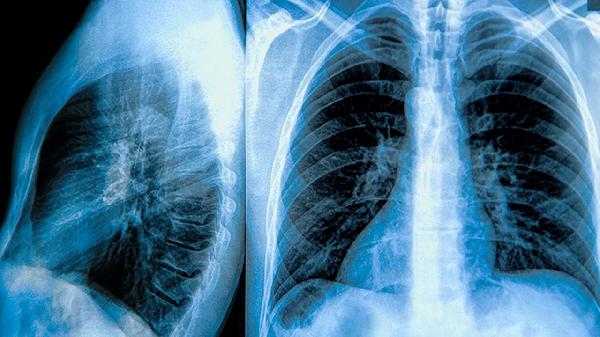

怎么治疗肺大泡

肺大泡的治疗方法包括药物治疗、手术治疗和生活方式调整,具体选择取决于病情严重程度和症状表现。药物治疗可采用支气管扩张剂、糖皮质激素和抗生素;手术治疗包括肺大泡切除术、胸腔镜手术和肺减容术;生活方式调整建议戒烟、避免剧烈运动和定期复查。